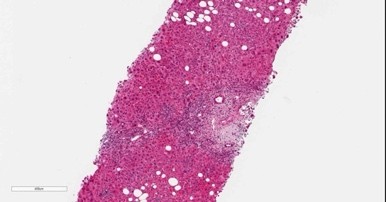

内視鏡センターとして、胃がん・大腸がん、食道がん・十二指腸がんの早期診断・治療に重点を置いています。早期がんに対しては、内視鏡治療(ESD:内視鏡的粘膜下層切開剥離術、EMR:内視鏡的粘膜切除術)を実施しています。これらの内視鏡治療は専門性が高く、外科手術に比べて負担が小さく入院期間も短期です.がん以外の疾患では、出血性胃潰瘍・十二指腸潰瘍、食道静脈瘤破裂、急性胆管炎、大腸・食道狭窄、嚥下障害に対して必要な内視鏡治療(止血術、胆管ドレナージ術、ステント挿入術、胃ろう造設術)を行っています。

肝疾患の診断・治療も重要です。慢性肝炎では、C型慢性肝炎に対する直接型抗ウイルス薬(DAA)によるIFNフリー抗ウイルス治療、B型慢性肝炎に対する核酸アナログ製剤(エンテカビル・テノホビル)治療の多数の経験があります。最近増えている脂肪性肝炎(SLD: MASH、 MASLD)を含めて、肝臓リハビリテーション、亜鉛補充、栄養療法(NST)、肝臓病教室、市民公開講座を通じて多職種がサポートする体制を構築しています。肝臓がんに対しては進行度や病状に応じて、ラジオ波焼灼療法やマイクロ波焼灼療法、外科手術、肝動脈塞栓化学療法併用、抗がん剤治療を選択しています。特に肝臓がんに対する超音波ガイド下治療では、CTやMRI画像を取り込み超音波画像と同期させ同一画面に表示する機能(Smart Fusion Imaging)を実装し、治療専用の穿刺用マイクロコンベックスプローブにより治療精度の向上を図っています。

肝生検23例